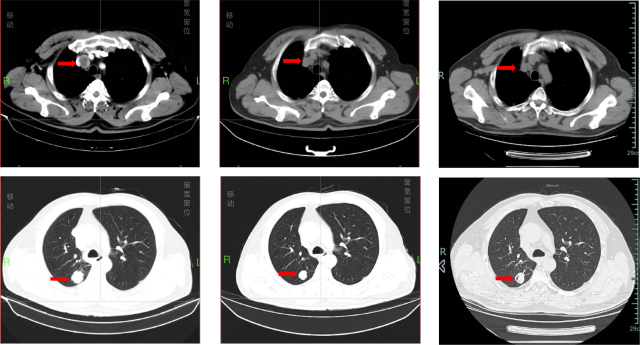

复查(2024.10.29)